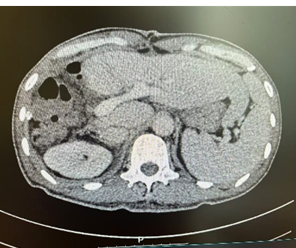

新辅助(两次HAIC和两个周期靶免治疗)后CT

新辅助(两次HAIC和两个周期靶免治疗)后MR

经术前三维成像评估右半肝切除后残肝体积为标准肝体积的50%,但吲哚箐绿(ICG)15分钟滞留率(ICG-R15)达25%,暂停手术,于是加强营养支持治疗,一周后复查ICG15分钟滞留率为14%,最后经肝胆胰外科专家组讨论不符合腹腔镜肝切除要求,决定行前入路右半肝切除术。右上腹斜切口进腹,探查见肝脏呈轻度肝硬化,两个肿瘤直径接近10.0cm的巨大肿瘤占据半肝,一个于包膜外可见,一个位于肝实质内,周围数个微小结节,未见肝内转移灶和腹腔转移灶,为避免术中不适当挤压引起肿瘤经血管转移和肿瘤破裂,先切断肝圆韧带和肝镰状韧带,解剖第二肝门,显露肝右和肝中静脉窝,然后切除胆囊,解剖第一肝门,鞘外分离右肝蒂,预阻断后见右肝缺血明显,除一个微小结节略偏向S4段外,肿瘤全部位于右肝缺血线内,于缺血性和S4段结节稍左侧约1.0cm画切肝线,术中超声证实肝中静脉位于切线下方、全部肿瘤位于切线右侧,结扎右肝蒂,以15+5min模式间歇性阻断肝门,原位离断左右肝之间肝实质,结扎切断肝断面血管和胆管,到达右肝蒂时确认右肝蒂后右切割闭合器离断右肝蒂,继续沿中肝静脉右侧离断肝实质,直至下腔静脉前壁,至此完全离断左右半肝之间的肝实质,然后于第三肝门显露、结扎、离断右侧肝短静脉,最后显露右肝静脉,切割闭合器离断右肝静脉,于Laennec膜外钝性分离肝裸区,离断右三角韧带和右冠状韧带,至此已原位肝切除术切除包括所有肝肿瘤的右半肝,移除切除物。肝癌切除术后余肝血运及回流良好,肝断面彻底止血后置橡胶引流管,关闭切口,术毕。